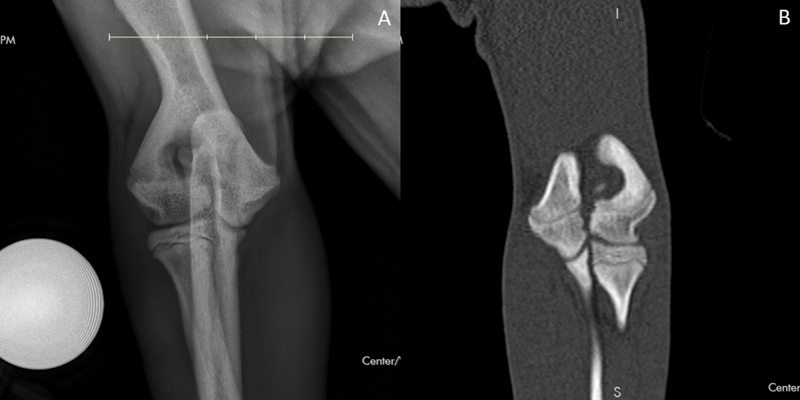

Objective:  The aim of this study was to report (1) the prevalence of contralateral humeral intracondylar GAP/HIF (HIF) in French Bulldogs with humeral condylar fractures (HCF) and (2) treatment and short- and long-term outcome in French Bulldogs with HCF.

Materials and methods:  Medical records of French Bulldogs treated surgically for HCF between January 2011 and November 2022 were reviewed. Perioperative imaging, surgical technique, complications, and long-term outcome were assessed.

Results:  Eighty-nine dogs with HCF were included and 36/89 were diagnosed with HIF. Surgical repair was performed in all HCF and a prophylactic transcondylar screw was placed in 20/36 HIF. For prophylactic transcondylar screw placement, two dogs required immediate revision surgery. Complications occurred in 12/89 HCF, and there were major complications in 6/89 HCF. Long-term outcome evaluated by owner questionnaire (n = 27) was rated as being excellent in 18/27 dogs, good in 8/27 dogs, and fair in 1/27 dogs.

Clinical significance:  Forty percent of French Bulldogs with HCF had a contralateral HIF. HIF as a cause of HCF should be considered in the French Bulldog, and a computed tomography (CT) scan of both elbows may be advisable prior to HCF repair. The complication rate of HCF surgery in the French Bulldog is significant.